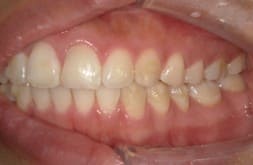

● 歯根が折れ保存不可の歯を抜歯して、そのスペースに八重歯を並べた症例

藤沢デンタルオフィスの虫歯や破折で抜歯後の部分矯正